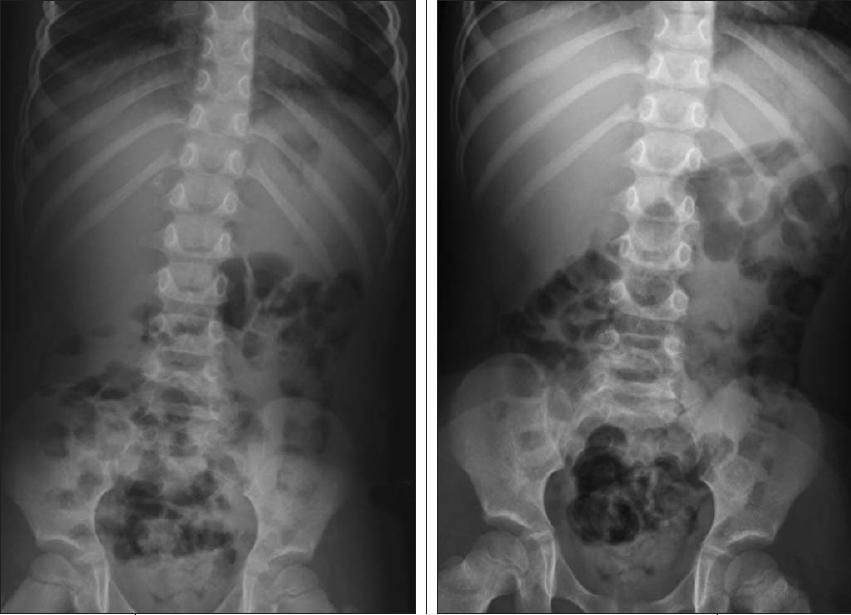

1. A 4-year-old girl was brought to the emergency department by her parents on a Sunday afternoon. Because of a clinical history of right upper quadrant pain and trace hematuria, abdominal radiographs were obtained. What do they show?

1. What do the abdominal radiographs show? (C is the correct choice.) Coarse clustered calcifications are seen in the right renal/ suprarenal area.

The bowel gas pattern is otherwise unremarkable. There is a moderate stool volume in the descending colon and rectum- much for a 4-year-old child-although this is not extraordinary. Bowel obstruction is not depicted